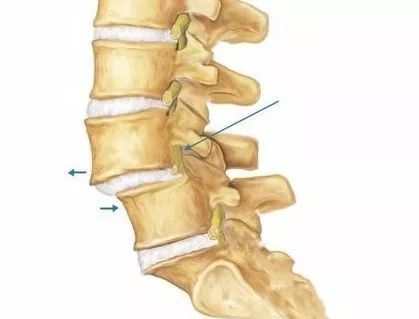

椎管壁的构成椎管是一骨纤维性管道,其前壁由椎体后面、椎间盘后缘和后纵韧带构成,后壁为椎弓板、黄韧带和关节突关节,两侧壁为椎弓根和椎间孔。

当闭管周围组织出现退变,增生,侵占了椎管的位置,就使它变得狭窄。就像软管被挤压,水流受阻,管道变形变窄一样。

腰椎有正常的生理曲线,但长期负重,不当坐姿下,可导致生理曲线变形,椎体之间不够稳定,发生错位滑脱。上下椎管前后移位,使椎管进一步变窄。这就像把水管的前后同时拉伸,中间的空隙就变窄了。

除了椎间盘膨出可以侵占椎管,管壁周围的组织都可能侵占它,从而导致狭窄。比如椎管后壁的黄韧带,关节突关节等,都会因为退变,劳损产生骨质增生或变厚,从而挤压了椎管。